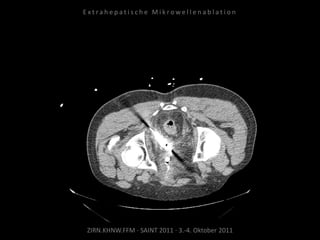

Metastase medial des linken

Musculus iliacus:

1 Nadelposition.